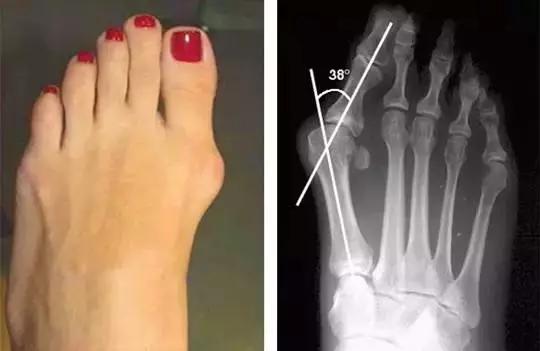

大脚骨是什么?拇趾外翻怎么办